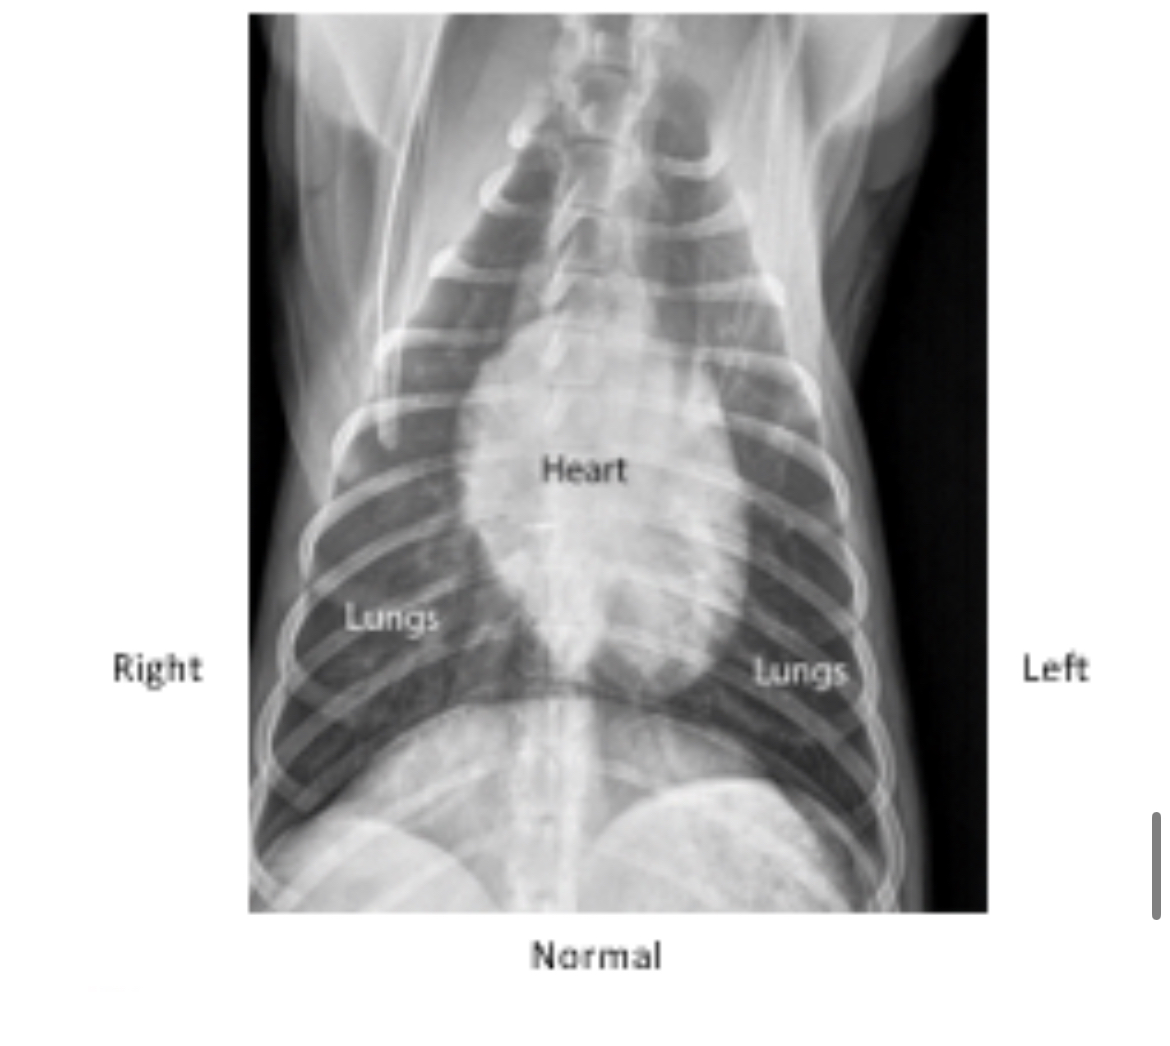

Examine this normal canine chest radiograph compared to Midnight's abnormal one. Which side of the heart appears enlarged?

Right